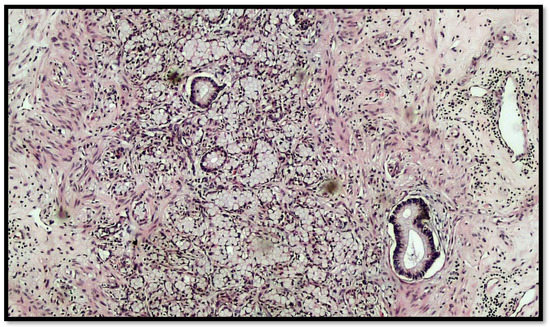

Figure 1.

Histological preparation of intestinal-type adenocarcinoma (black arrow) arising on villous adenoma with high grade dysplasia (red arrow) (hematoxylin–eosin, original magnification: 10×).